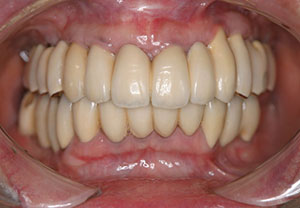

治療後

16年後全てのインプラント安定してます

【症例1 57歳 女性 上顎前歯の違和感】

| 治療内容 | 主訴:上顎の前歯部分が疼痛により当院へ相談しに来院されました。 処置:骨が欠損していた難症例でしたので、帆年再生療法(GBR)と歯肉移植を併用したインプラント治療を行いました。十分な骨の再生が得られ、きれいな歯が入ったと喜ばれました。 |